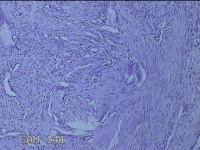

宫颈赘生物

性别

女

年龄

55岁

临床诊断

一般病史

发现宫颈赘生物一个月。

标本名称

大体所见

灰白粉红色肿物1.8x1.3x0.7cm一个,表面糜烂,切开肿物呈实性,切面灰白粉红色,质软。